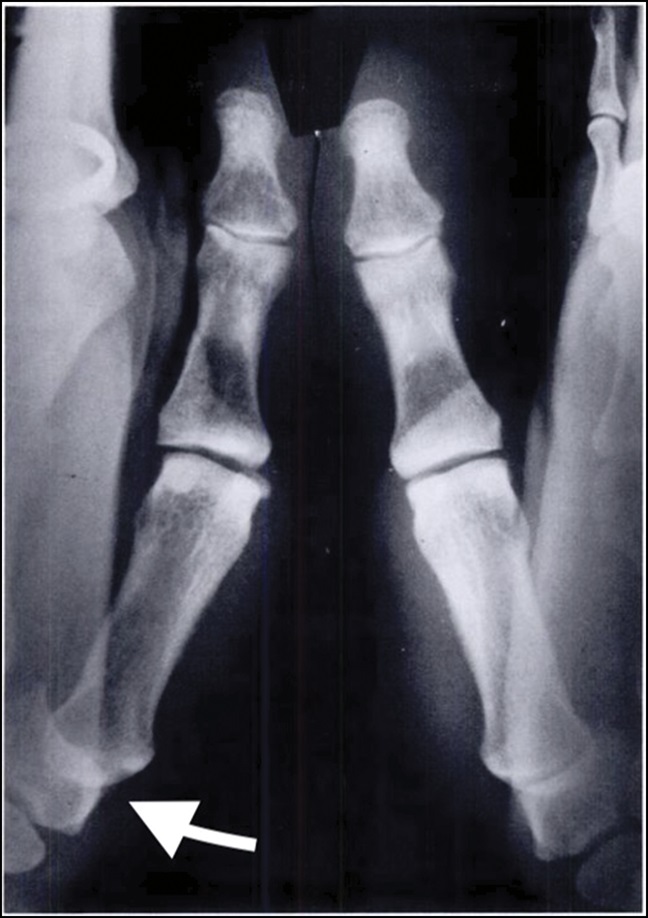

• Placing a temporary pin or a permanent suture (stitch) from the thumb metacarpal to the index finger metacarpal to keep the thumb metacarpal in place

X-ray of a hand after thumb CMC arthroplasty with removal of the trapezium. In this patient, thumb metacarpal positioning is maintained by permanent suture with suture buttons.